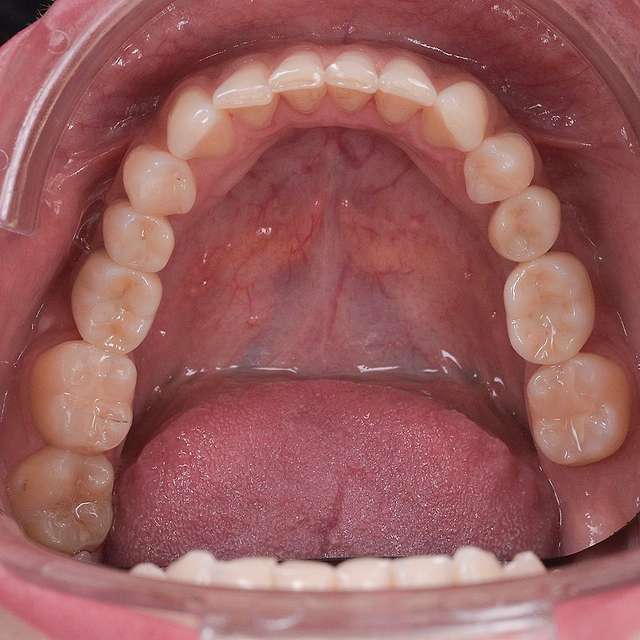

Digital design and planning

For optimal esthetic results, the final design must always be the refference for the surgery. This design together with the CBCT of the patient are compiled to find the ideal position of the dental implants.